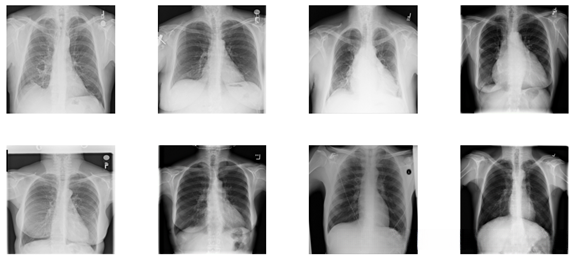

本文主要介绍了通过深度学习进行肺部病变识别的应用,首先简单介绍了影像学医学背景和相关知识,接着介绍了目前能获得的公开的肺部病变数据集,最后介绍了神经网络的实现方式和处理后的效果以及性能分析,其中涉及到了多特征识别的问题。

数据是从美国国立卫生研究院临床中心临床PACS数据库中提取的,其中正前位的胸片占医院所有正前位胸片总数的60%。因此,这个数据集更具代表性。

数据集包括112120张前视图X射线图像,分别对应14个疾病图像标签。

其中包括14种常见的肺部病理:肺不张(Atelectasis)、实变(consolidation)、浸润(Infiltration) 、气胸(pneumothorax) 、水肿(edema) 、肺气肿(emphysema) 、纤维化(fibrosis) 、渗出(effusion) 、肺炎(pneumonia) 、胸膜增厚(pleural thickening) 、心肥大(cardiomegaly) 、结节(nodule) 、肿块(mass )、疝气(hernia) 。